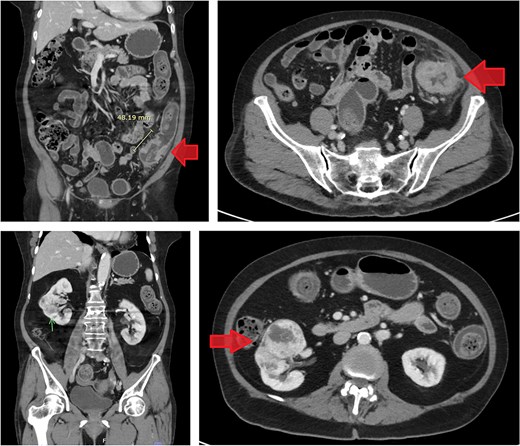

CT scan of the abdomen revealed a short segment of irregular, circumferential wall thickening at the distal descending colon, measuring 1.8 cm in thickness and extending 4.8 cm in length. Moreover, it was associated with an adjacent soft tissue lesion and perilesional fat stranding. Chest CT imaging demonstrated the absence of lymph node enlargement and pulmonary metastatic lesions. Incidentally, a 6.6 cm heterogeneous, hypervascular mass was detected in the interpolar region of the right kidney, abutting the anterior renal fascia (Fig. 3).

Contrast-enhanced CT images of case 2. Top-left: Coronal view of the sigmoid colon cancer. Top-right: Transverse view of the CRC. Bottom-left: Coronal view of the RCC. Bottom-right: Transverse view of the RCC.

Similar to the previous case, the imaging findings were suggestive of synchronous dual primary malignancies involving RCC and sigmoid colon cancer. Both cases were co-managed by urologists and general surgeons. Magnetic resonance imaging was not conducted in either case, as the findings from abdominal and chest CT scans, along with EGD and colonoscopy, provided sufficient evidence to support the clinical diagnosis and guide management.